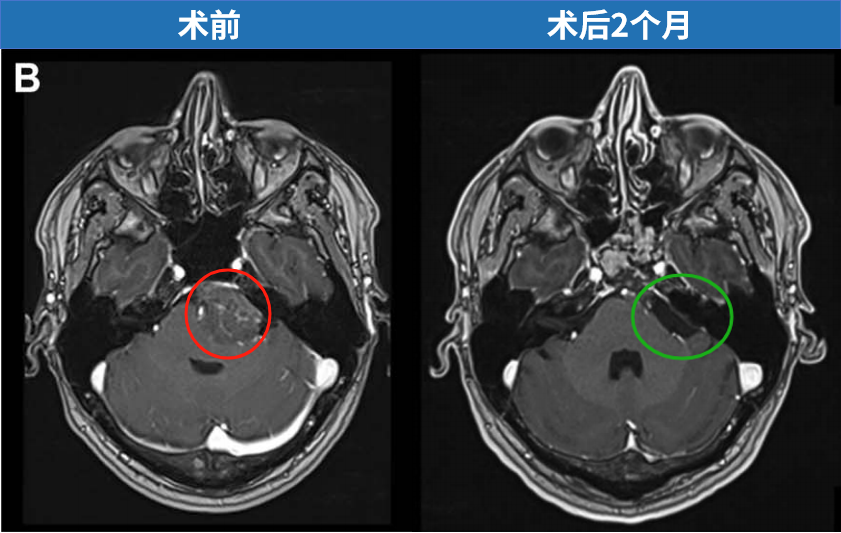

案例一:尺寸为29×39×38 mm的大型岩斜区脑膜瘤,肿瘤体积如小山丘状,顶部直接压迫"生命禁区"脑干,并与神经血管结构紧密粘连。患者初期仅表现为头痛症状。

需要明确的是,岩斜区脑膜瘤的大小每增加1cm,手术难度相应提升。鉴于肿瘤位置险要且体积较大,多数观点认为需通过开颅手术才能实现全切。然而,在INC福教授制定的个体化手术策略下,无需开颅,仅通过右侧单鼻孔入路便实现肿瘤全切。术后脑干复位良好,未出现脑脊液漏及新发神经功能障碍。

为何症状如此严重?2014年确诊岩斜区脑膜瘤后,考虑到肿瘤属良性且手术风险,患者选择保守观察。然而经过6年时间,肿瘤持续生长压迫脑干,症状进行性加重。福教授采用开颅手术方案,术前通过线圈在咽升动脉处进行栓塞,显著减少术中出血。肿瘤切除过程中使用CUSA刀进行逐步减瘤。术后MRI显示肿瘤接近完全切除,脑干受压解除。